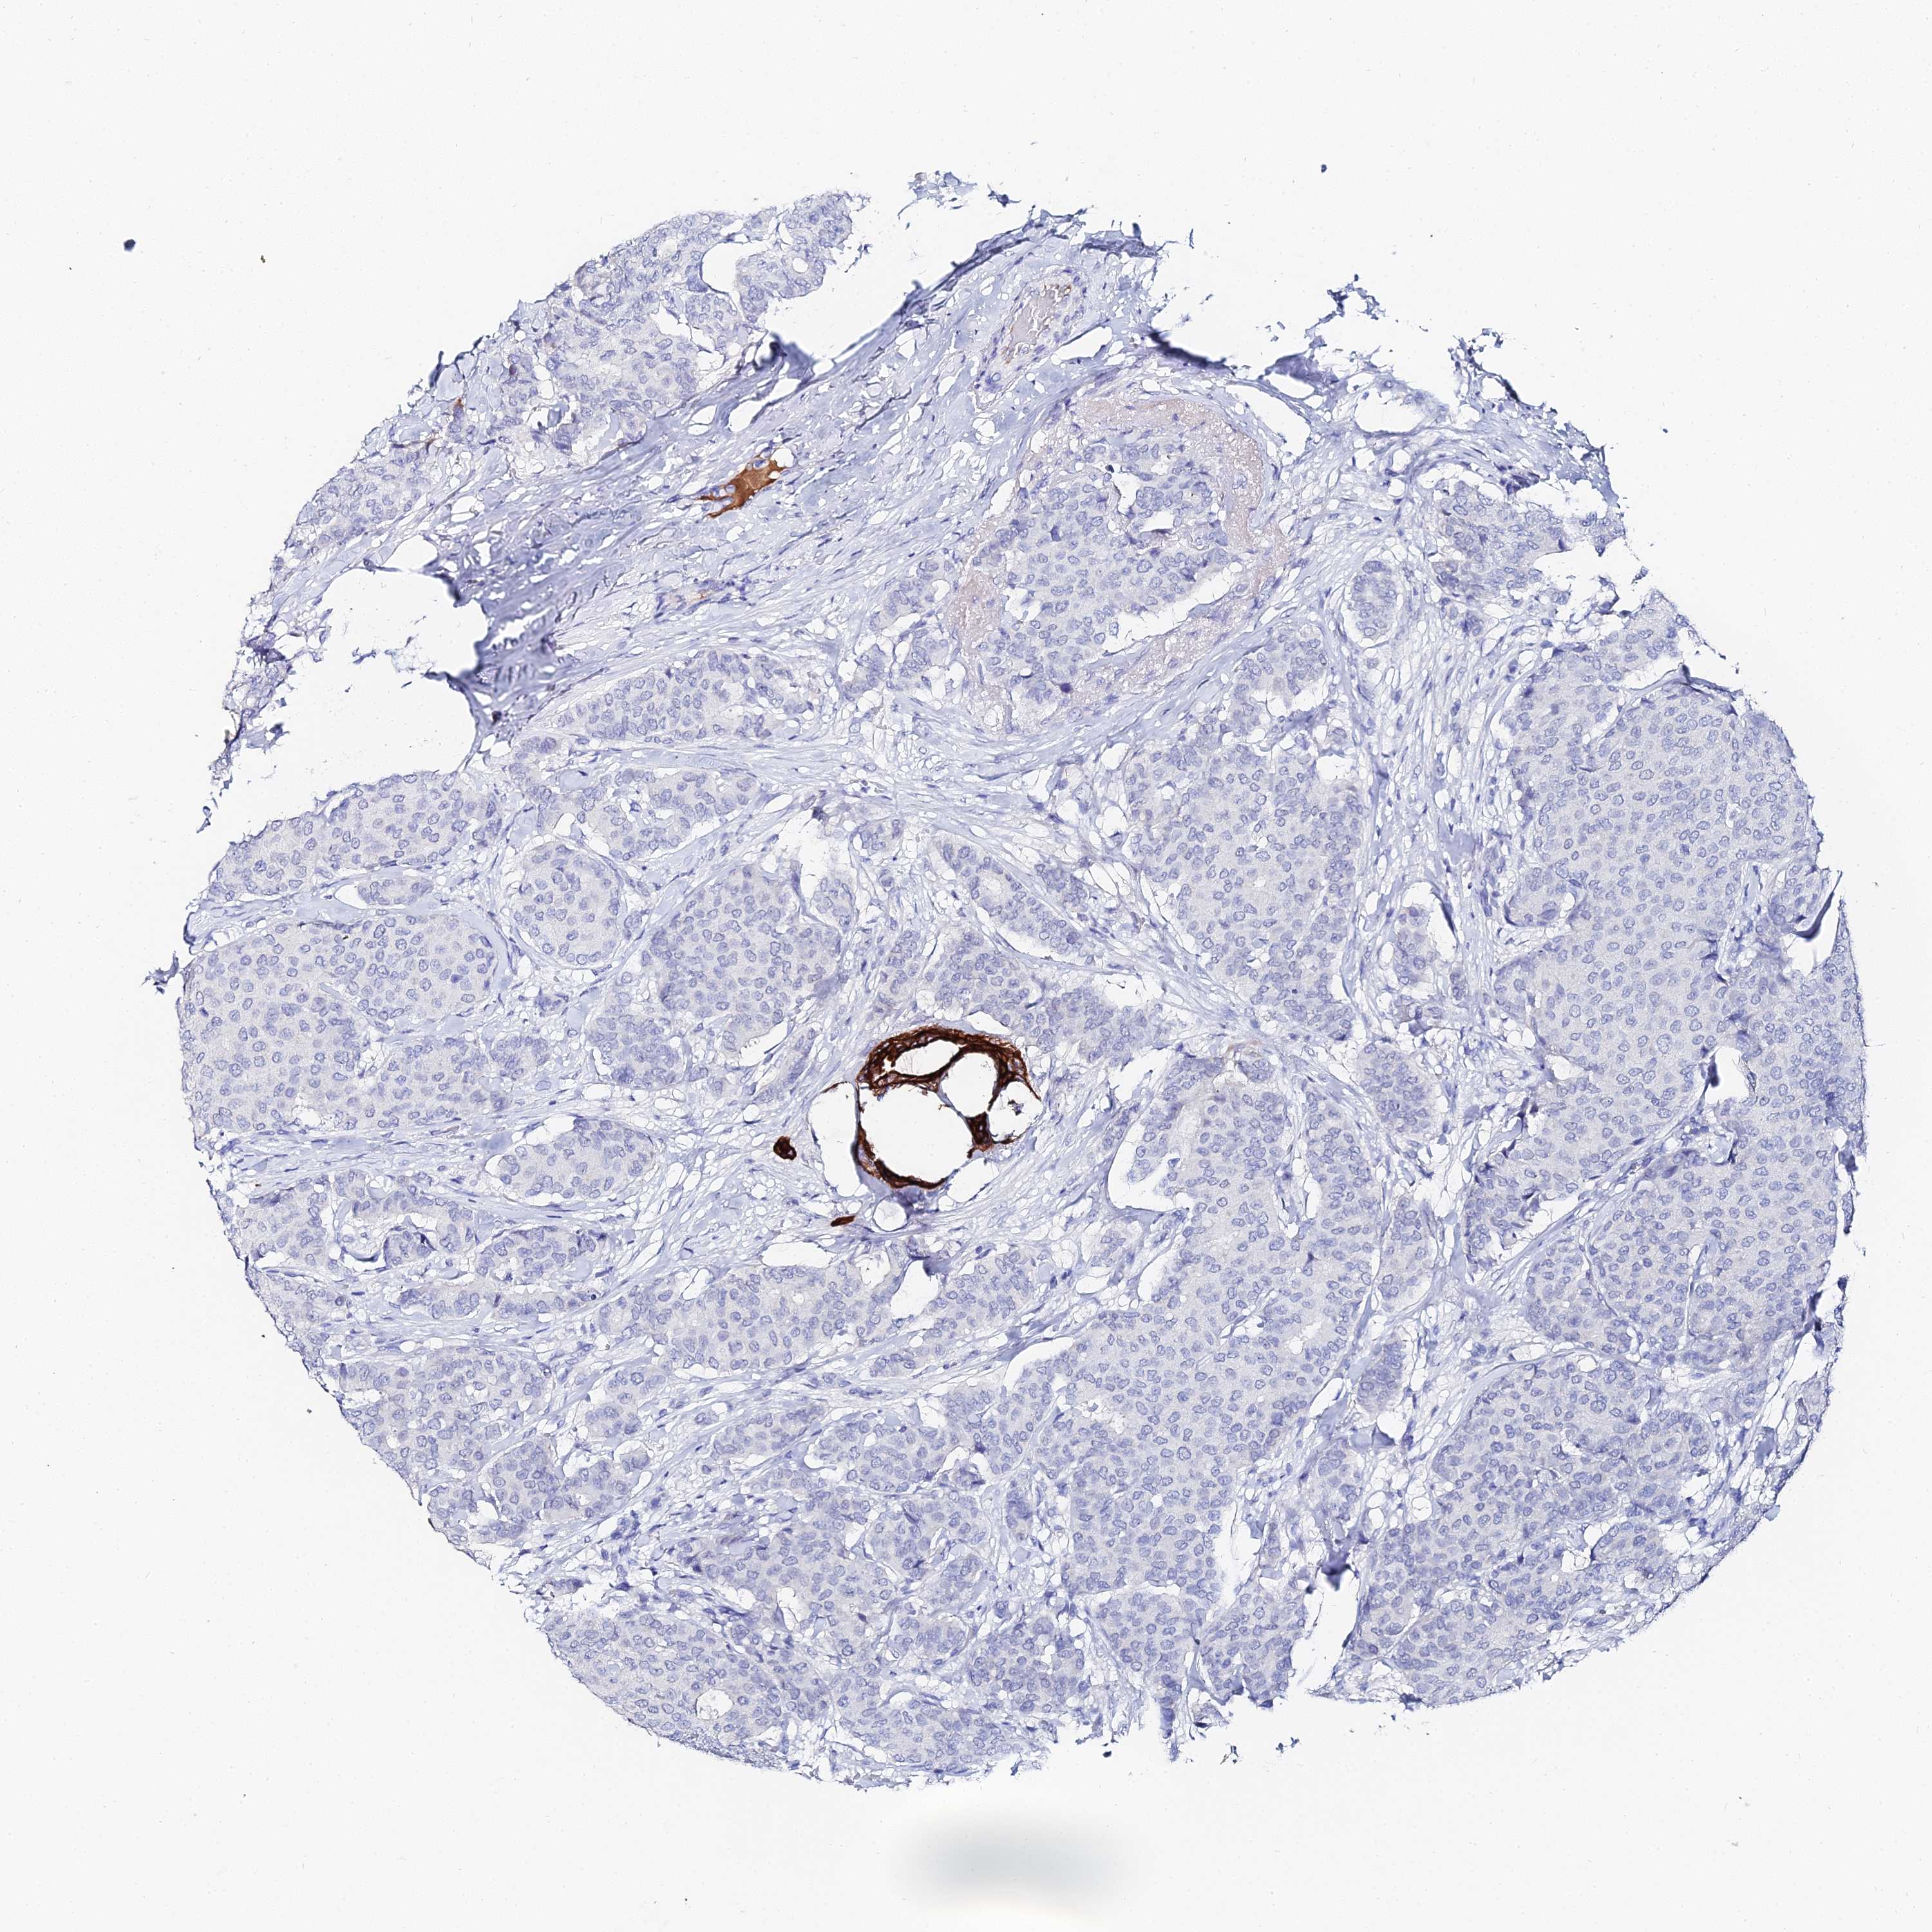

KRT17

CANCER BREAST CANCER Show tissue menu

BRCA TCGA BRCA VALIDATION PROTEIN EXPRESSION

ANTIBODIES

AND

VALIDATION